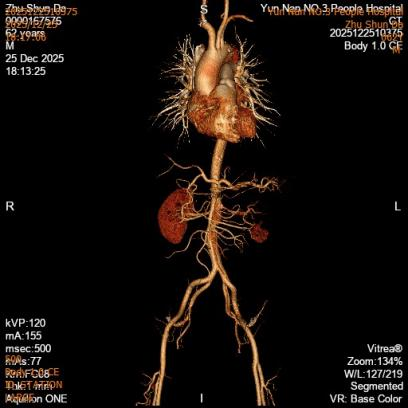

第二例患者诊断为胸腹主动脉夹层(Debakey Ⅲ型,逆向撕裂至主动脉弓部)。治疗团队先行采取非手术方案促进血肿吸收,再限期行腔内修复术。术中运用院内新技术“支架体外开窗”,成功保留了左侧锁骨下动脉血供;同时,腹主动脉覆膜支架采用术中自制微孔设计,在实现真腔扩大的同时,进一步减少了对脊髓血供的影响。

第二例患者术前CT